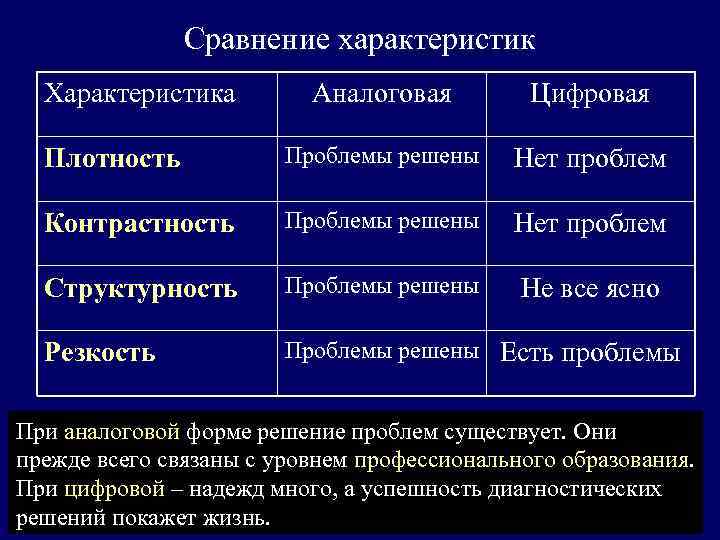

Сравнение характеристик Характеристика Аналоговая Цифровая Плотность Проблемы решены Нет проблем Контрастность Проблемы решены Нет проблем Структурность Проблемы решены Не все ясно Резкость Проблемы решены Есть проблемы При аналоговой форме решение проблем существует. Они прежде всего связаны с уровнем профессионального образования. При цифровой – надежд много, а успешность диагностических решений покажет жизнь.